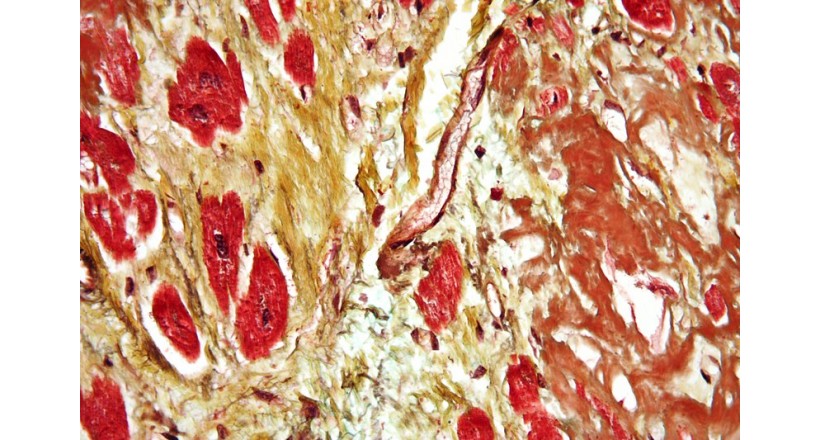

Cardiovascular disease class of diseases involving the heart or blood vessels (arteries and veins). While the term technically refers to any disease affecting the cardiovascular system (as used in the headings of medical subjects MeSH), it is commonly used to refer to arterial diseases, such as ( atherosclerosis ). These conditions have the same causes, mechanisms, and treatments. In practice, cardiovascular diseases are treated by the heart, chest surgeons, vascular surgeons, neurologists, radiologists' interventions, depending on the organ system. There is an overlap of specialties, and it is common that some procedures have to be different types of specialists in the same hospital .Most Western countries face high and increasing rates of cardiovascular disease. Every year, heart disease kills many Americans more than cancer . Cardiovascular disease alone causes 30% of all deaths, and cardiovascular disease causes disability in addition to death. Two out of three deaths from heart disease occur without any diagnosis of cardiovascular disease. [4] Until 2005 , these diseases were the No. 1 cause of death and disability in the United States and most European countries . One large histological study (PDAY) showed that vascular injury accumulates from adolescence , making it necessary to make primary prevention efforts from childhood